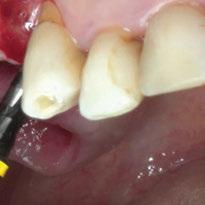

Para ilustrar el proceso, presentamos el caso de una mujer joven diagnosticada de carcinoma adenoide quístico en la región posterior del hemipaladar izquierdo (Figuras 1 y 2). El procedimiento quirúrgico realizado fue una

maxilectomía parcial que incluyó las piezas 24-26 y desde el reborde alveolar hasta la base del cráneo (Figuras 3 y 4). En este caso, la órbita y el globo ocular pudieron ser preservados. La reconstrucción inmediata se realizó mediante un colgajo de músculo temporal homolateral (Figura 5) y el defecto de la fosa temporal fue cubierto mediante una malla de titanio. Posteriormente, la paciente recibió radioterapia (Figuras 6 y 7). 2 años más tarde se diseñó un IS con anclaje en el arbotante nasomaxilar, zona subnasal izquierda

Figura 1. Imagen preoperatoria de la paciente.

Figura 2. Carcinoma adenoide quístico en región posterior del hemimaxilar izquierdo.